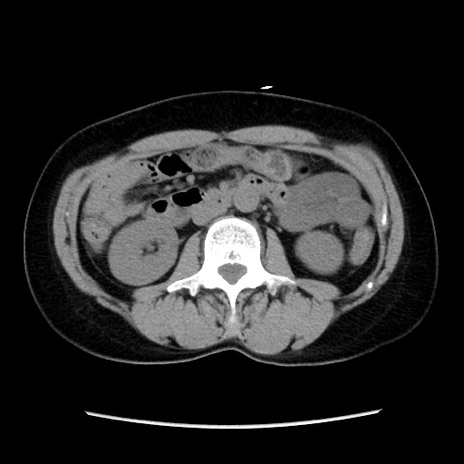

症例10(横断像)

【症例】 50歳代女性

【主訴】 腹痛

【現病歴】前日生レバーを食べた。今朝に排便あり。 昼前に突然発症の腹痛を生じ、当院救急外来を受診した。

【既往歴】 子宮筋腫にてで子宮全摘後

【身体所見】 意識清明、腹部:平坦、軟、下腹部やや左を中心に圧痛・反跳痛あり、筋性防御あり

【データ】WBC 7800、CRP 0.07